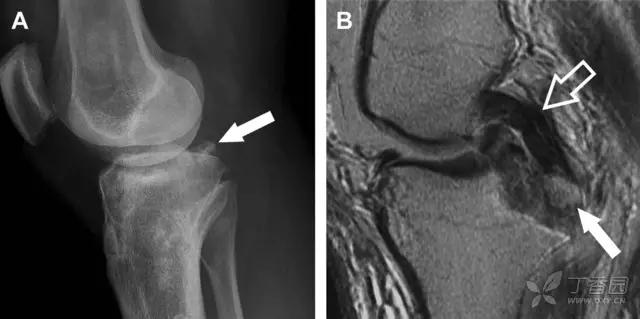

9 股骨外侧髁凹陷征

图 2 扭伤后的股骨外侧髁凹陷征

A 侧位片示股骨外侧髁凹陷。B MRI 矢状位 T2 加权像示股骨外侧髁及胫骨后外侧骨挫伤(空箭头)。胫骨近端随着后交叉韧带撕裂发生移位,露出外侧半月板的后角(弧形箭头)。